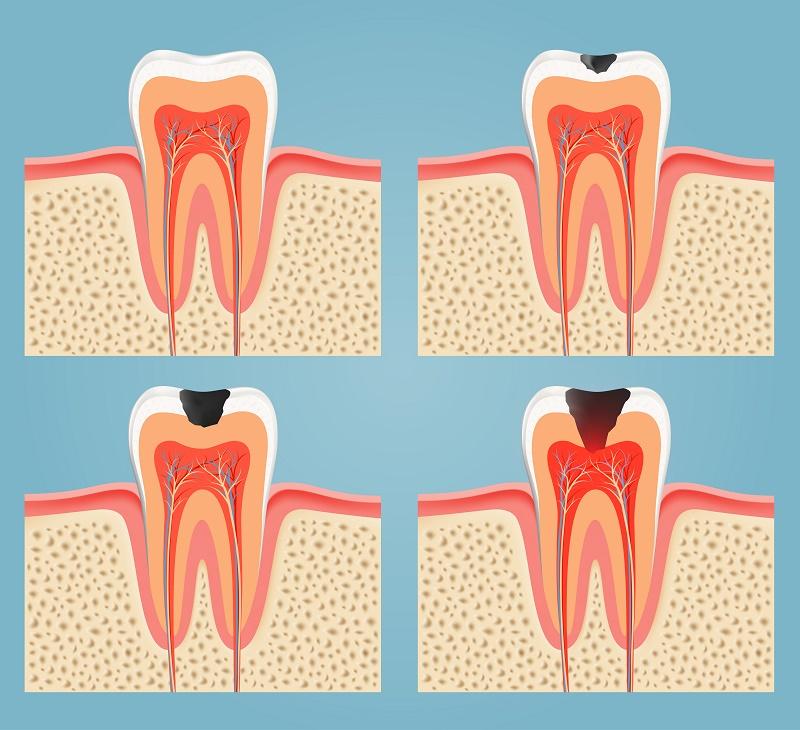

Caries que debilitan por completo el diente

Las caries son la causa de visita al odontólogo más común, se producen por una acumulación de placa en el diente que, al no ser eliminada adecuadamente, comienza a afectar el esmalte dental y a producir orificios en el mismo. En un principio el paciente no notará nada, pero si la infección llega a la pulpa dental sin ser atendida comenzará a afectar los nervios causando dolor y molestias. Una vez que la caries alcanza los ligamentos del hueso dental producirá abscesos e infecciones, haciendo que el tejido del diente se debilite y que acabe por quedar inutilizado e incluso caerse.

Una caries sin tratamiento pone en riesgo de forma notable la salud del diente, por lo que siempre debe atenderse y tratarse para evitar perder el diente, lo que tendría consecuencias mayores.